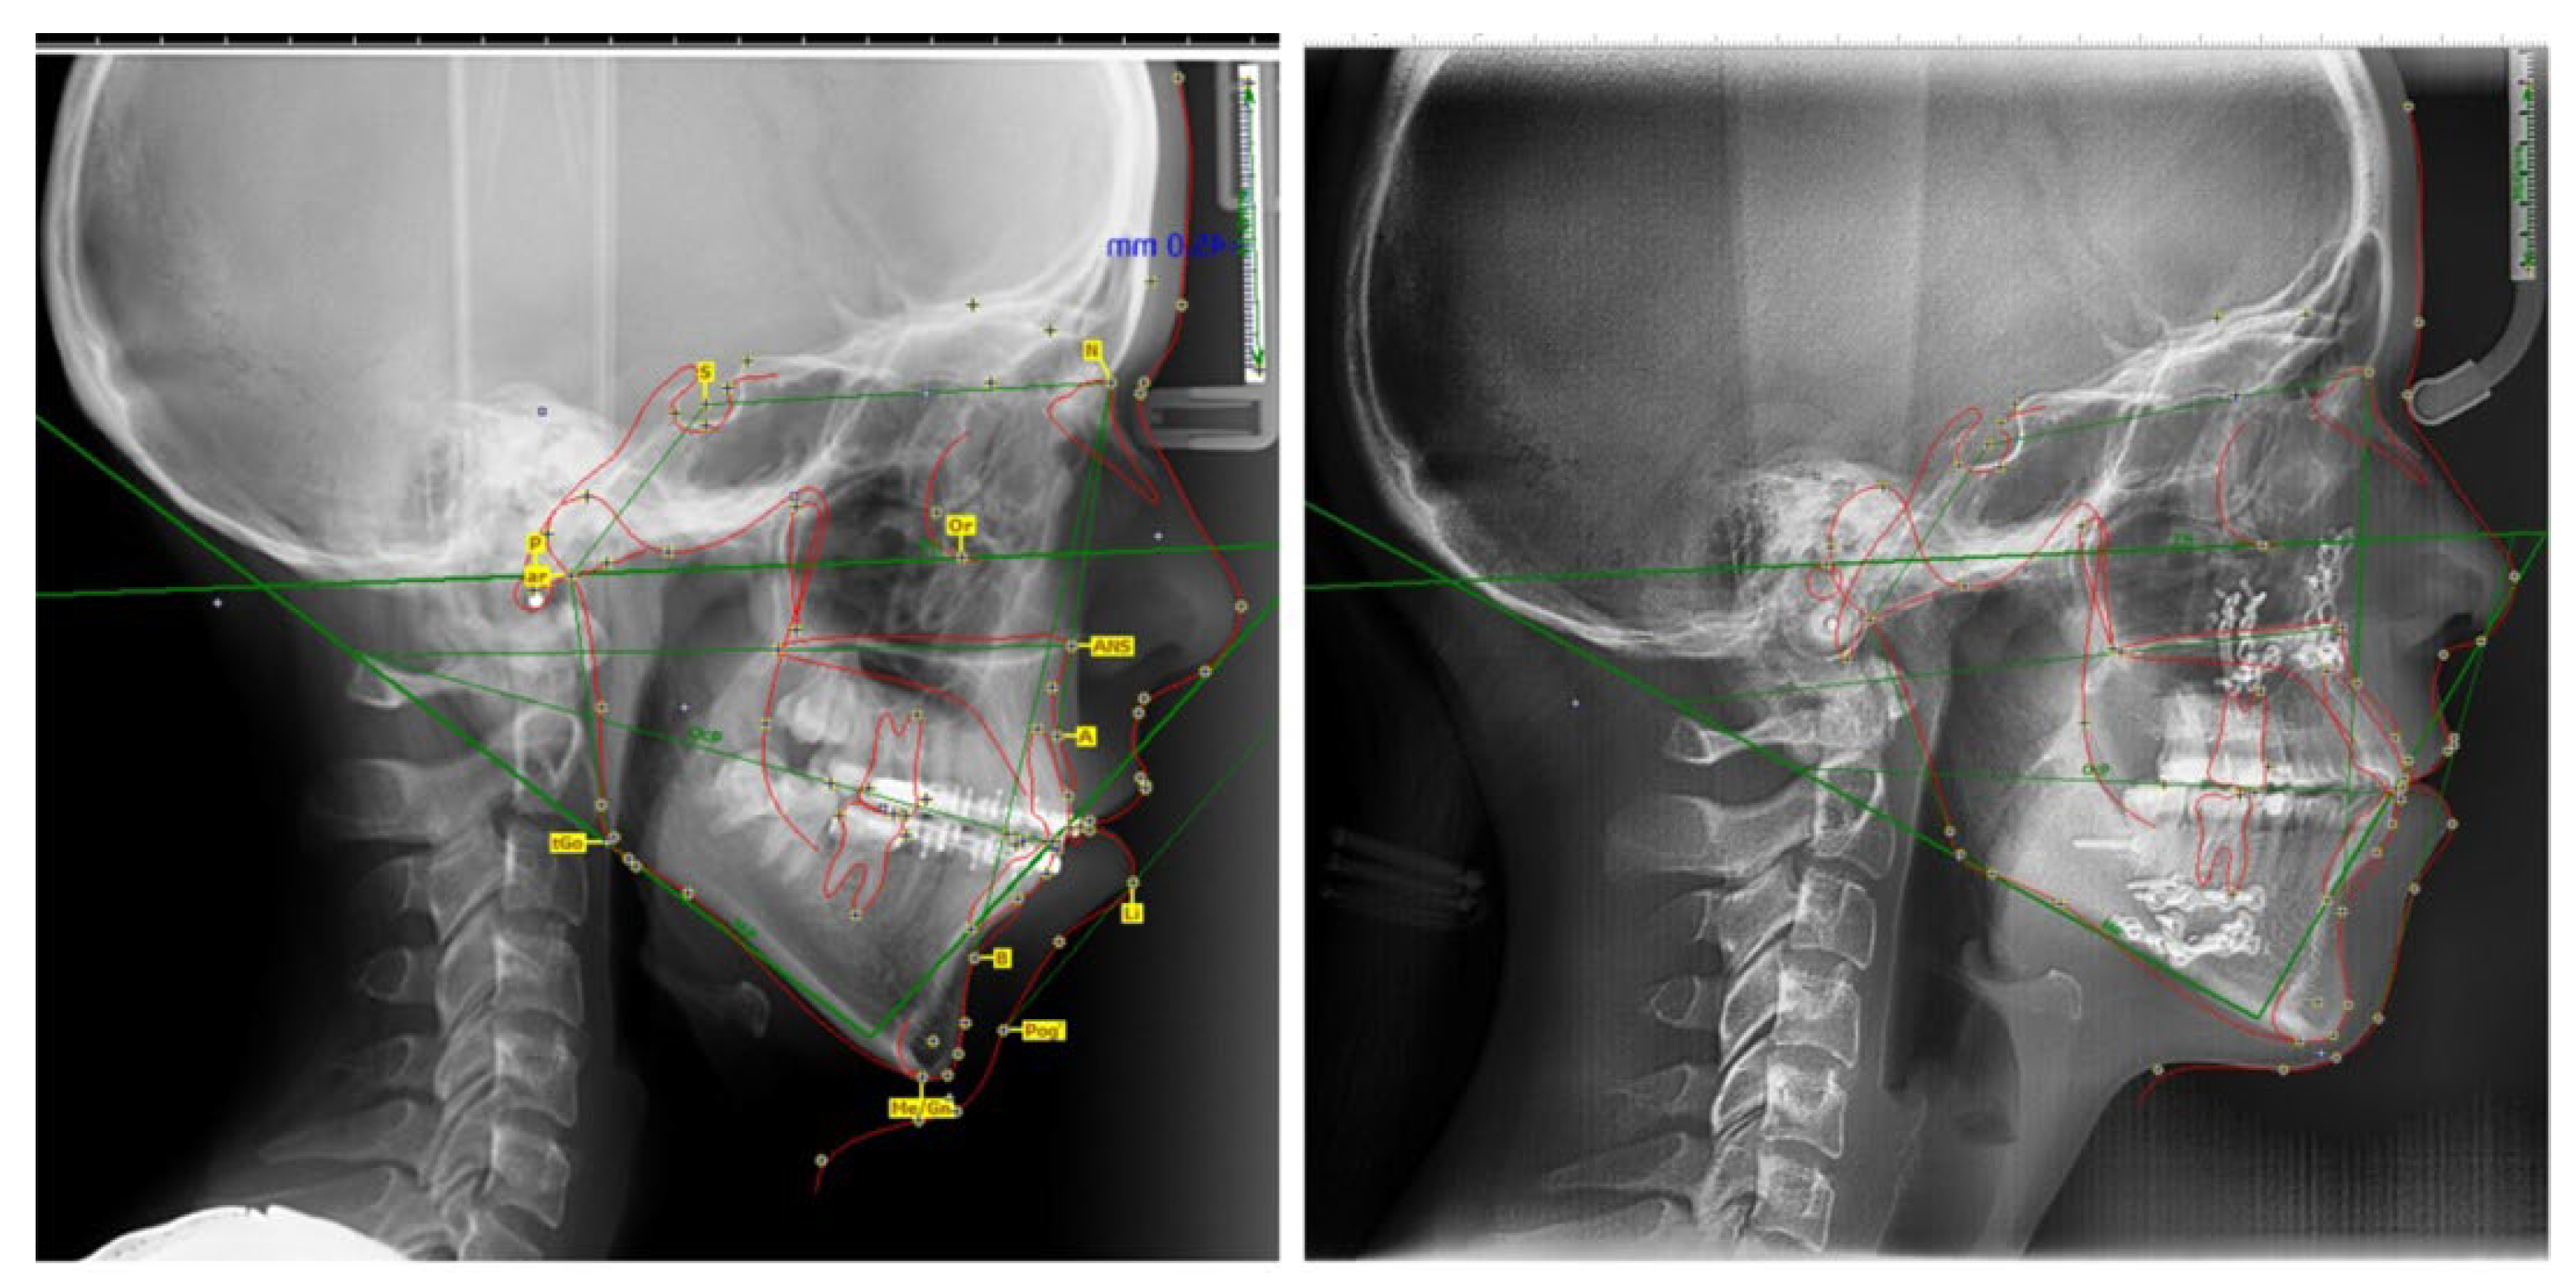

- Skeletal open bite in a 15.7-year-old patient with hyperleptoprosop morphological facial type (N-Gn/Zy-Zy = 111.66), high degree of hyperdivergence (FMA = 39.22°), bimaxillary dento-alveolar protrusion (IF = 120.85°, IMPA = 98.03°), 7 mm skeletal open-bite, and 3 mm vertical inocclusion of the anterior teeth;

- Skeletal class II relationships (SNA = 78.32°, SNB = 73.98°), bilateral half cusp class II molar and canine relationships;

| Parameters | Normal Values | Pre- Treatment | Before Orthognatic Surgery | After Orthognatic Surgery | Differences |

|---|---|---|---|---|---|

| FMA | 25 ± 3° | 39.22° | 36.13° | 28.23° | 10.99° |

| IMPA | 88 ± 3° | 98.03° | 93.22° | 91.14° | 6.89° |

| SNA | 82 ± 2° | 78.32° | 78.17° | 80.35° | −2.03° |

| SNB | 80 ± 2° | 73.98° | 74.12° | 78.22° | −4.24° |

| IF | 107° ± 5° | 120.85° | 107.32° | 111.80° | 9.05° |

| HFP/HFA | 0.69 | 0.52 | 0.54 | 0.64 | 0.12 |

| Upper lip length (mm) | 23.4 ± 3.42 | 14.5 | 14.7 | 16.8 | 2.3 |

| FMI | 81.9 | 111.6 | 110.2 | 84.3 | 27.3 |

| U1-SN | 103 ± 7° | 115.12° | 104.78° | 109.50° | 5.62° |